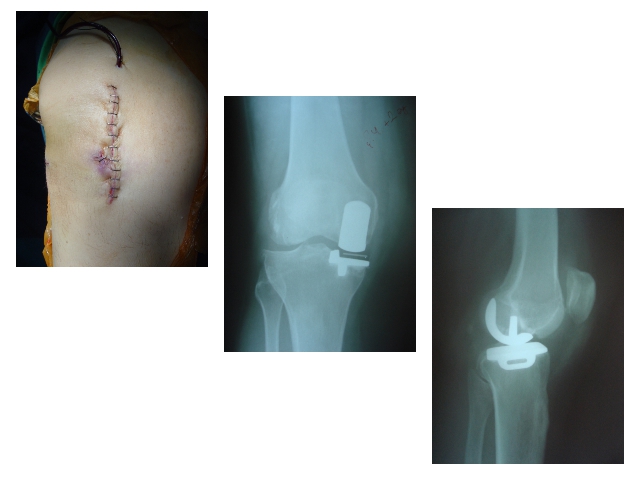

Hip and Knee ProsthesisDec 30, 2021 | Case ExamplesKnee Prosthesis Revisions Total Knee Prosthesis Unikondiler